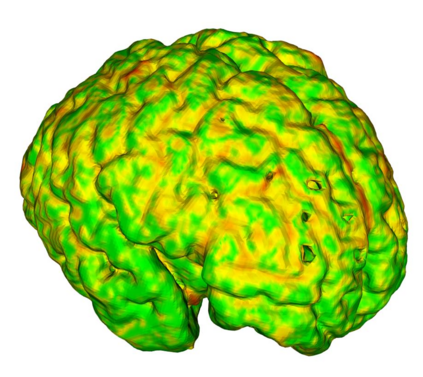

Fetal cortical plate segmentation is essential in quantitative analysis of fetal brain maturation and cortical folding. Manual segmentation of the cortical plate, or manual refinement of automatic segmentations is tedious and time-consuming. Automatic segmentation of the cortical plate, on the other hand, is challenged by the relatively low resolution of the reconstructed fetal brain MRI scans compared to the thin structure of the cortical plate, partial voluming, and the wide range of variations in the morphology of the cortical plate as the brain matures during gestation. To reduce the burden of manual refinement of segmentations, we have developed a new and powerful deep learning segmentation method. Our method exploits new deep attentive modules with mixed kernel convolutions within a fully convolutional neural network architecture that utilizes deep supervision and residual connections. We evaluated our method quantitatively based on several performance measures and expert evaluations. Results show that our method outperforms several state-of-the-art deep models for segmentation, as well as a state-of-the-art multi-atlas segmentation technique. We achieved average Dice similarity coefficient of 0.87, average Hausdorff distance of 0.96 mm, and average symmetric surface difference of 0.28 mm on reconstructed fetal brain MRI scans of fetuses scanned in the gestational age range of 16 to 39 weeks. With a computation time of less than 1 minute per fetal brain, our method can facilitate and accelerate large-scale studies on normal and altered fetal brain cortical maturation and folding.